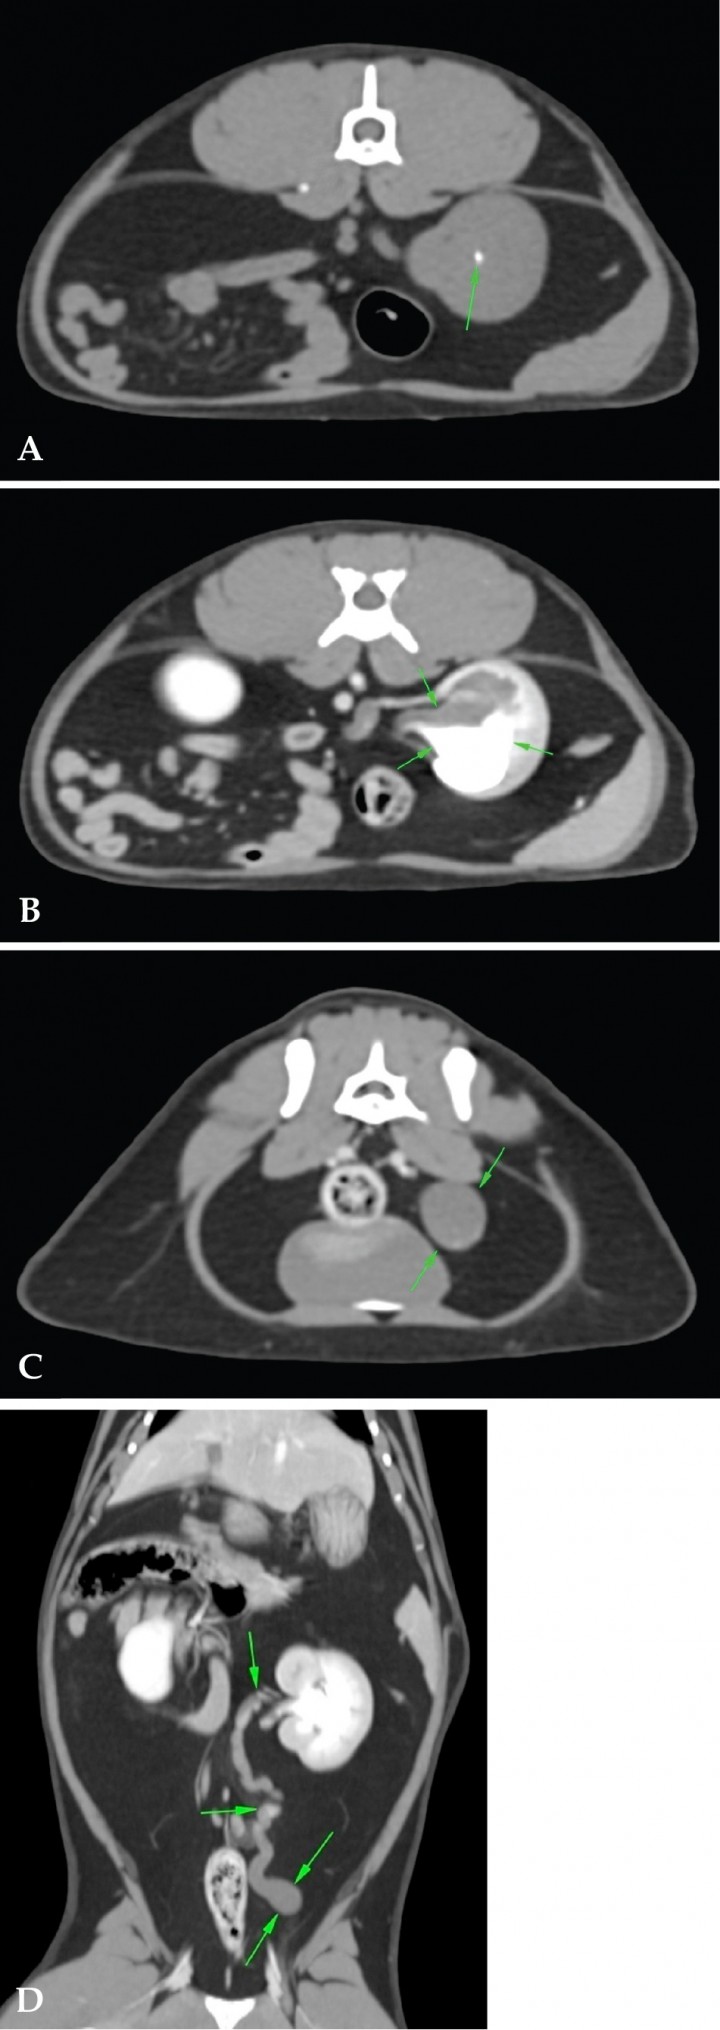

Para caracterizar estos hallazgos se realizó una tomografía computarizada (TC) abdominal en fases pre y postcontraste. En el estudio precontraste, se observaron dos nefrolitos de pequeño tamaño en pelvis renal izquierda (Fig. 4A), hidrouréter e hidronefrosis en riñón izquierdo (Fig. 4B) y una dilatación bulbosa máxima de 1,3 cm justo antes de la unión ureterovesical izquierda (Fig. 4C). Estos hallazgos hicieron que se descartara la presencia de engrosamientos o masas en la entrada a la vejiga de la orina, así como la presencia de uréter ectópico o ureterocele. En el estudio postcontraste se observó un drenaje deficiente del uréter izquierdo y ausencia de cálculos ureterales (Fig. 4D).

<p>(A) Imágenes de TC precontraste. Plano transversal. Se aprecia un nefrolito de pequeño tamaño (flecha verde). (B) Imágenes de TC postcontraste. Plano transversal. Se observa hidronefrosis e hidrouréter (flechas verdes) y dilatación bulbosa en la unión ureterovesical (flechas verdes). (C) Plano transversal. Ausencia de engrosamientos o masas (flechas verdes). (D) Plano dorsal. Drenaje deficiente del uréter izquierdo (flechas verdes).</p>

(A) Imágenes de TC precontraste. Plano transversal. Se aprecia un nefrolito de pequeño tamaño (flecha verde). (B) Imágenes de TC postcontraste. Plano transversal. Se observa hidronefrosis e hidrouréter (flechas verdes) y dilatación bulbosa en la unión ureterovesical (flechas verdes). (C) Plano transversal. Ausencia de engrosamientos o masas (flechas verdes). (D) Plano dorsal. Drenaje deficiente del uréter izquierdo (flechas verdes).

El hallazgo más relevante de la TC fue la evidencia de un hidrouréter izquierdo grave y crónico, asociado a hidronefrosis obstructiva desde la unión ureterovesical izquierda; no se evidenciaron cálculos ureterales o vesicales en dicha exploración. En este punto, descartadas las neoplasias y una ligadura iatrogénica del uréter, se consideraron la estenosis ureteral como causa más probable y una estenosis secundaria a episodios anteriores de urolitiasis (menos probable).